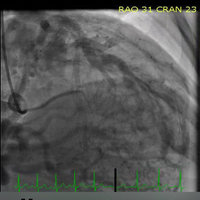

* Searchable database containing more than 30 videos (coronary angiograms, ventriculograms, and aortograms) of both common and rare findings in the cardiac catheterization lab

* Searchable database of over 65 images including hemodynamic formulas, tables, and figures

CathSource provides a detailed overview of important cardiac catheterization and angiography topics, incorporating educational images/videos as well as reviews of pertinent medical literature.

CathSource is the ideal application to assist you in understanding and recognizing cardiovascular pathology in the catheterization lab.